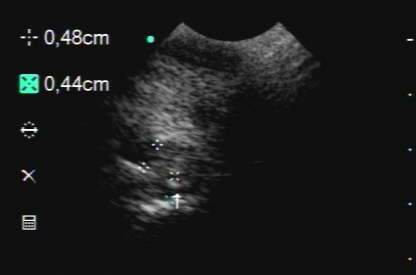

Ultraschall

Normaler Weichteilbefund am Strahlbein mit fraglicher Gewebsverdichtung am unteren Strahlbeinband